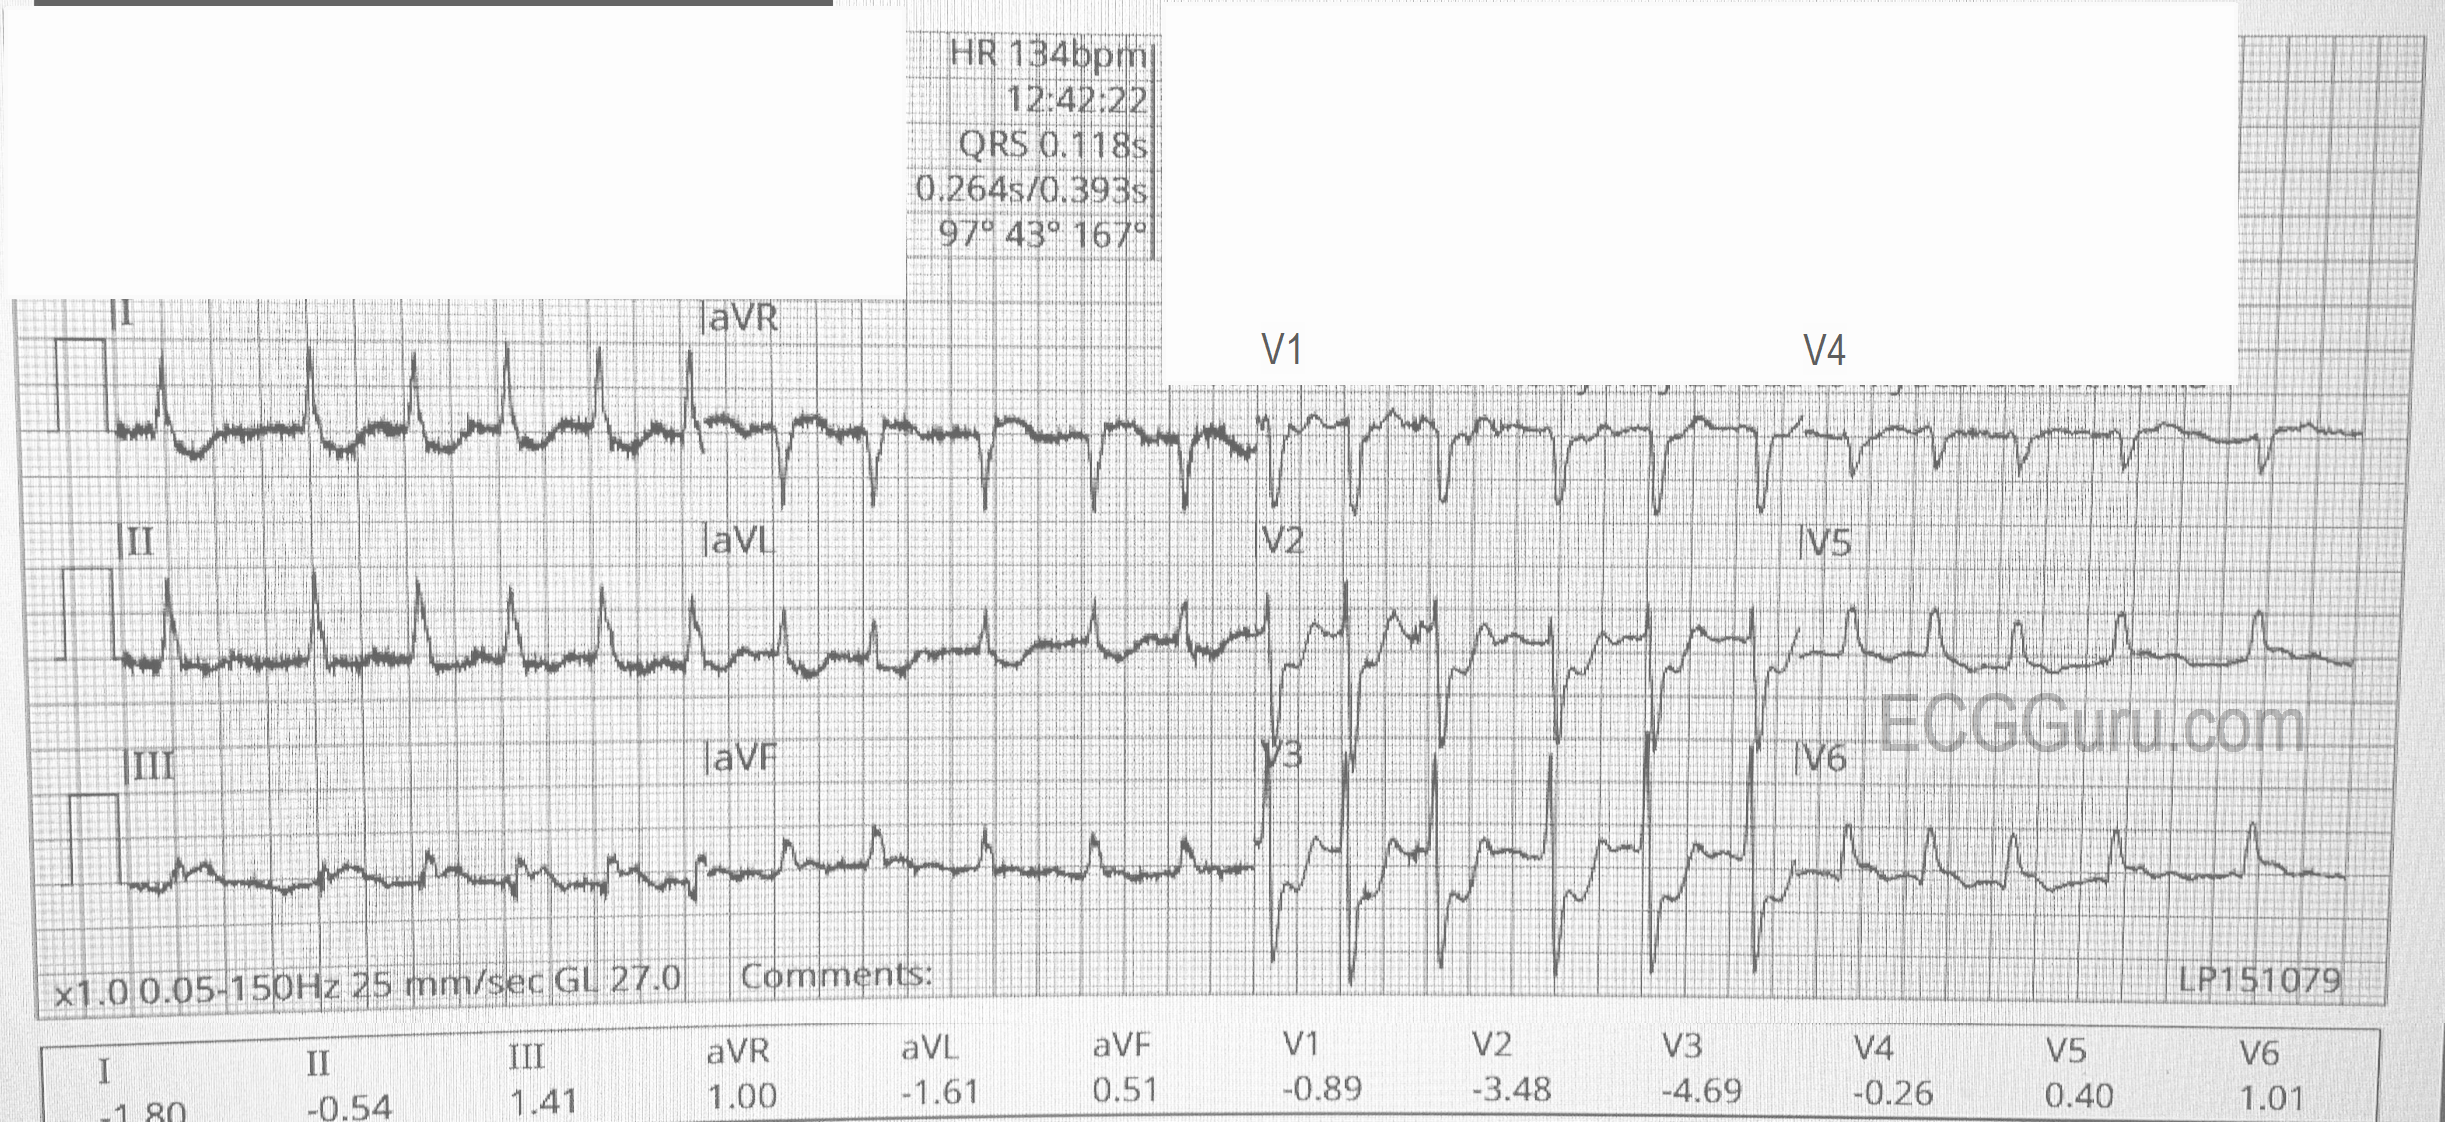

The ECG (from EMS):

The rhythm is atrial fibrillation with a rapid ventricular response (about 134/min.). The QRS width is .118 seconds (118 ms).  The frontal plane axis is slightly to the left, but WNL. The R wave progression mostly normal, but V4 is incongruous.  V2 and V3 have a tall R wave, possibly representing a pathological Q on the posterior side.  There are ST CHANGES in every lead. ST elevation is noted in III, aVF, aVR, V5 and V6, representing ischemia in the inferior wall. There is ST depression in all other leads, indicating widespread subendocardial ischemia and/or acute reciprocal depression.  Interesting that Lead II would normally be elevated when III and aVF are, but aVR is elevated, causing reciprocal ST depression in Lead II.  So, Lead II looks almost normal.

The pattern of ST elevation in aVR with widespread ST depression can indicate:

1)     Proximal occlusion of LAD or significant stenosis of Left Main artery.